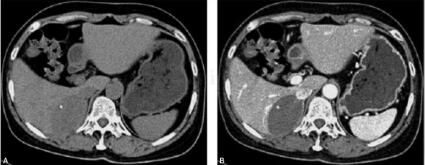

患者女,56岁,以“发现右肾上腺占位3天”为主诉入院。查体:T:36.6℃,P:76次/分,R:16次/分,BP:140/83mm Hg。患者双肾区无叩痛,双侧输尿管走行区未及明显压痛,膀胱区无明显隆起,未及包块,无压痛叩诊无浊音(图1、图2)。

图2 腹部CT平扫及增强。A图:平扫CT;B图:增强CT动脉期;C图:增强CT静脉期。右侧肾上腺区类椭圆形软组织密度影,密度欠均匀,内见点状钙化灶,最大截面约6.1cm×4.3cm,边界清楚,增强扫描未见明显强化